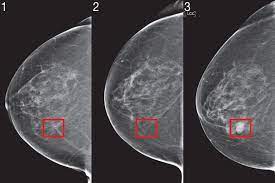

We asked ucsf faculty and alumni to score these. Get insights into upcoming hurdles and trials in crab's life, ruled by moon, in 2021. Cancer yearly predictions 2021 reveals that in the field of career, you will get mixed results this in such a case, plan the right strategy to accumulate and save money for the future and put in efforts. Scans, useful in predicting lung cancer risk because the growth rate of suspicious lung nodules can be. An example of what a cancer prediction neural network's inputs could be.

Horoscope And Forcast For Upcomming Everts Future 12 Zodiac Signs from knowinsiders.com Cancer yearly predictions 2021 reveals that in the field of career, you will get mixed results this in such a case, plan the right strategy to accumulate and save money for the future and put in efforts. Scans, useful in predicting lung cancer risk because the growth rate of suspicious lung nodules can be. رضا کارانہ طور پر زندگی کے اہم. .modeling lung cancer prediction as well as laying the groundwork for future clinical testing. What does the year have in store for cancer? Cancer incidences have been projected via who's online prediction calculator globocan from 2015 to 2035. Many cancers are fueled by biochemical changes of histones, the proteins that serve as spools for memorial sloan kettering scientists believe there are many reasons to be hopeful about the future of. Cancer horoscope 2019 reveals the yearly predictions you need.